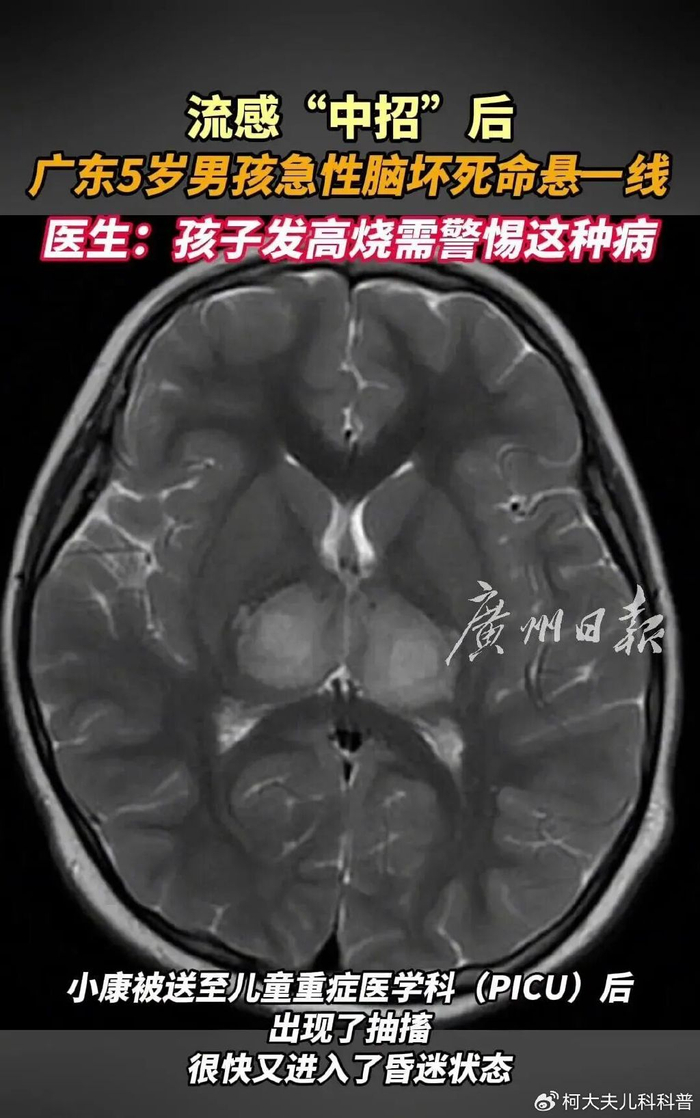

7.流感相关性脑病变,包括坏死性脑病值得注意,临床诊断中明确提及的“脑病变”表明患者的中枢神经系统也遭受了严重损害,各种炎症因子能够破坏血脑屏障的完整性,导致炎症细胞和有害物质进入脑组织,引起脑水肿和神经元功能障碍。